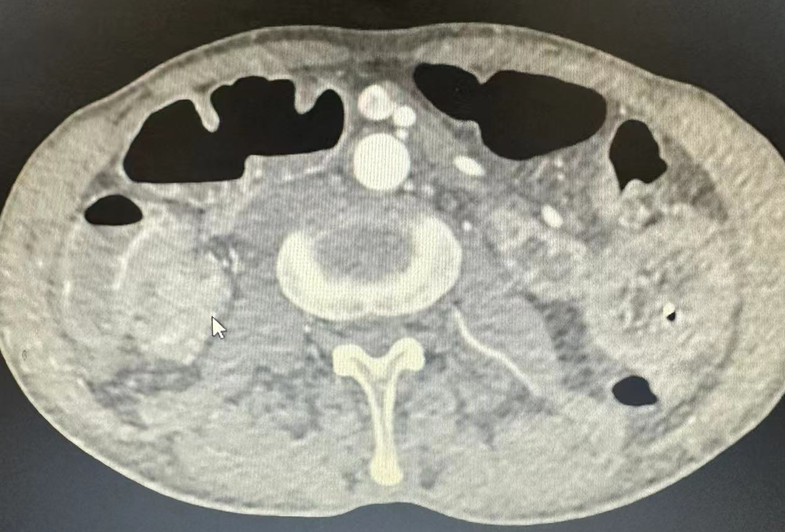

患者为66岁男性,1周前无明显诱因下开始出现阵发性中下腹胀痛,进食后有恶心呕吐,偶有腹泻。外院就诊予以行腹部CT检查,提示小肠梗阻,回盲部肠壁局部明显增厚,占位性病变待排。进一步完善肠镜检查,提示结肠占位性病变(待病理),结肠息肉。经MDT讨论,术前予以肠梗阻导管减压桥接治疗,并拟行腹腔镜下右半结肠癌根治术+小肠排列术。

术前腹部CT图